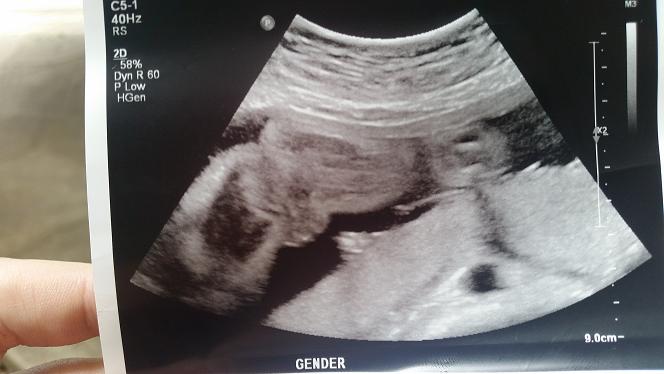

Hi can someone help me what they think the sex of baby is - I thought girl from the "three lines" one but the other one is throwing me because it looks protruding... they are both from the same scan but my area dont tell you sex of the baby so frustrating!!!

Thank you x

Attachment 38992Attachment 38993